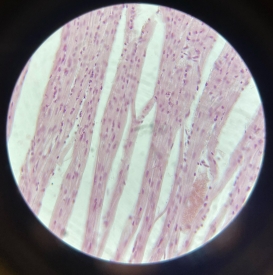

Cardiac Muscle

Cardiac Muscle

Cardiac Muscle

Cardiac Muscle

Cardiac Muscle